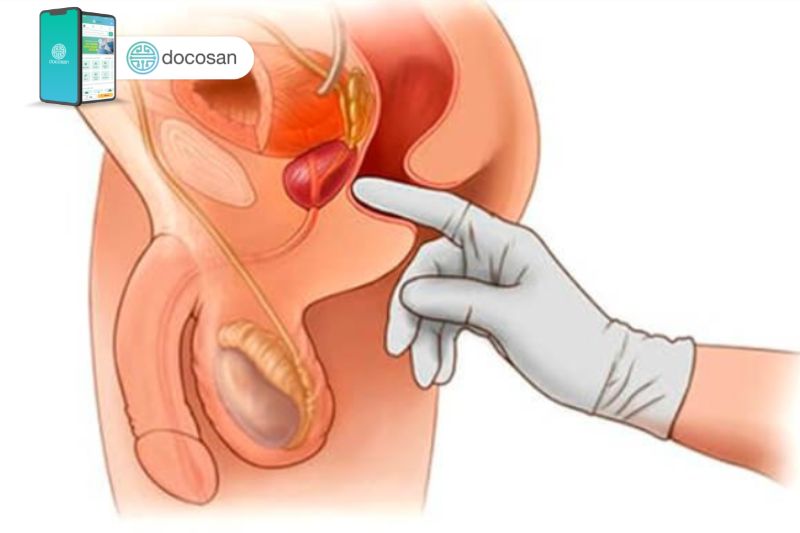

Tiền liệt tuyến là cơ quan sinh dục của nam giới có vai trò sản xuất hầu hết các chất có trong tinh dịch, từ đó làm chất dịch màu trắng sữa nuôi dưỡng và vận chuyển tinh trùng khi xuất tinh. Vị trí nằm bên dưới bàng quang và tiếp xúc trực tiếp với ống vận chuyển nước tiểu từ bàng quang sẽ đi qua trung tâm của tiền liệt tuyến.

Hầu hết nam giới sẽ được tiếp tục tăng trưởng tiền liệt tuyến trong suốt cuộc đời và sự tăng trưởng này trực tiếp gây ra u phì đại tiền liệt tuyến. Nếu kích thước u đủ lớn và gây chèn ép sẽ gây ra các triệu chứng tiết niệu do gây tắc nghẽn đáng kể lưu lượng nước tiểu. Các bác sĩ nam khoa không chắc chắn chính xác nguyên nhân làm cho tiền liệt tuyến ngày càng to ra, có thể là do những biến đổi sự cân bằng của hormone sinh dục nam của người lớn tuổi.